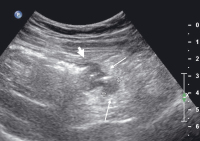

Kolon-Divertikulitis: Diagnostik und sonographisch gesteuerte Therapie

Journal für Gastroenterologische und Hepatologische Erkrankungen 2009; 7 (2): 13-18 Volltext (PDF) Summary Praxisrelevanz Fragen zum Artikel Abbildungen